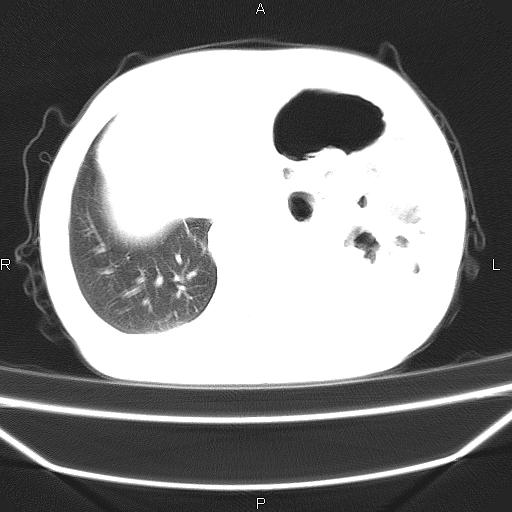

患者,男。50岁。近几日有咳嗽症状,无其他不适,既往病史无,考虑膈疝。请前辈们看看指导指导。

膈膨升,左下肺通气不良,膈肌好像还完整。

考虑左侧膈疝。

左侧膈疝。

符合隔膨升,膈肌较完整。